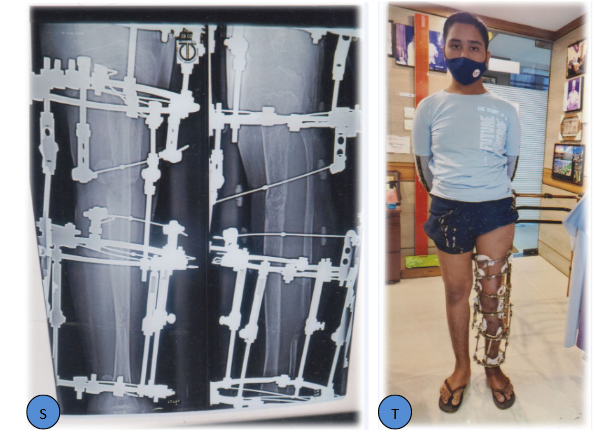

Citation: Bari MM, Shahidul I, Tanvir A, et al. Post traumatic genu valgum with valgus deformity of left lower femur and upper tibia valgus and procurvatum deformity with 10cm L. L. D and puckering of skin around knee with bad scar. MOJ Orthop Rheumatol. 2021;13(3):43-46. DOI: 10.15406/mojor.2021.13.00546

Post-traumatic femoral valgus and upper tibia valgus and procurvatum deformity with 10cm LLD were corrected with Ilizarov Technique. The lower femur deformity correction and deformity correction of upper tibia and lengthening were carried out simultaneously. This case demonstrates an approach to large complex post-traumatic deformity in the left knee region with puckering of the skin and bad scar.

A 14 years old boy sustained motor vehicle injury in the left inferior extremity at the age of 8. He was treated at Combined Military Hospital, Dhaka at that time because father is an Army personnel. Now, he was referred to Bari-Ilizarov Orthopaedic Centre for further management, that is for correction of deformity and L. L. D. Plain X-ray and clinical ndings showed his left lower extremity with distal femur valgus deformity, proximal tibia valgus and procurvatum deformity. He was complaining left knee pain and his gait was awkward. His father was anxious regarding his deformity correction and lengthening of left lower limb.1–5

Figure 1 A-J 14 years old boy, Post Traumatic Genu Valgum with Valgus Deformity of left Lower Femur and Upper Tibia Valgus and Procurvatum Deformity with 10cm L. L. D and Puckering of Skin around Knee with Bad Scar.

Everything must be done gradually. In Ilizarov technique gradual distraction is always preferred when amount of deformity is large and bone lengthening is necessary. Here the skin is very bad with bad scar and puckering is obvious.6,7

Figure 1 K-T